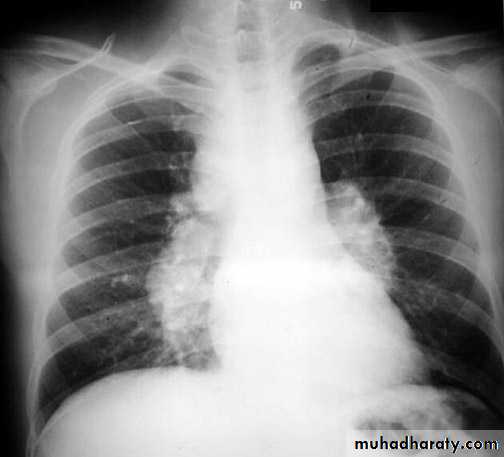

Alveolar pulmonary edema